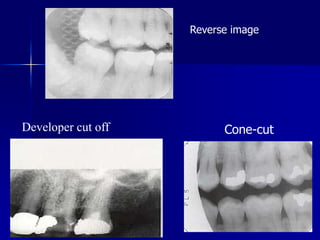

This is uncomfortable for the patient and may produce an inadequate view of the teeth and surrounding bone. The Benefits of a Cone Beam X-Ray. A cone beam takes a 3-D image of your teeth soft tissue nerve pathways and bone with just one scan. The other region of the X-ray is clear with the structures seen clearly. Instead you get x-ray vision. Cone-cut kōnkŭt Manifestation visible in a dental radiograph in which a portion of the image is missing due to the radiation beams having been blocked by improper aim of the cone or position-indicating device qv.

Bitewings show teeth above the gum line and the height of the bone between teeth. The shape of the cone-cut depends on the type of collimator used when exposing the receptor. This angulation is derived from the average vertical angulation of the maxillary and mandibular teeth when in occlusion and allows the x-rays to strike the film at a 90 degree angle providing the most accurate representation of the teeth on the film with maximal overlap of the buccal and lingual alveolar crests and cusps of the teeth. The most common being the image receptor is not in line with the position indicating device PIDradiographic coneHence the collimator which reduces the size and shape or cross-sectional area of the X-ray beam doesnt completely exposes the film resulting in cone cut. Round Cone Cut Rectangular Cone Cut.

Projection errors PID alignment artifact If the PID is misaligned and the x-ray is not centered over the film a partial image is seen on the resultant radiograph this partial image is called cone-cut. The shape of the cone-cut depends on the type of collimator used when exposing the receptor. This results from the x-ray beam not positioned perpendicular over the film. This is uncomfortable for the patient and may produce an inadequate view of the teeth and surrounding bone. Three simple rules serve to identify and correct any errors.

The attenuated x-rays are detected on the opposite side by an x-ray detector which has multiple dexels in the x and y-axis 2. Cone-cut kōnkŭt Manifestation visible in a dental radiograph in which a portion of the image is missing due to the radiation beams having been blocked by improper aim of the cone or position-indicating device qv. A cone beam x-ray can get a more accurate picture than a conventional x-ray. So if you have white space on the mesial aspect. Medical Dictionary for the Dental Professions Farlex 2012 Want to thank TFD for its existence.

When using digital imaging the cone-cut appears as an opaque or white area. Receptor instruments with beam guides facilitate beam centering over the receptor when properly assembled. If you cut the target off at the edge of the beam cone cut simply move the beam over toward the area of cone cut. Cone cut errors are caused by not centering the x-ray beam over the receptor. PDF In routine dental radiography one may encounter numerous radiographic errors one of which may be partial images or cone cuts.

The attenuated x-rays are detected on the opposite side by an x-ray detector which has multiple dexels in the x and y-axis 2. PDF In routine dental radiography one may encounter numerous radiographic errors one of which may be partial images or cone cuts. A cone beam takes a 3-D image of your teeth soft tissue nerve pathways and bone with just one scan. Cone cut appearance Cone cut appearance refers to a clear unexposed area in a dental radiograph. Phalangioma The term phalangioma was used by Dr.

Cone cut may be caused by various reasons. It can be. Dental x-rays are taken with you sitting upright in a chair. Cone-cuts appear as a clear zone on traditional radiographs after processing due to the lack of x-ray exposure in the area of the cut. Instead you get x-ray vision.